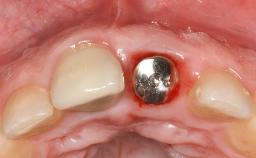

In this case, Myroslav Solonko, Ignacio Sanz Sánchez and Mariano Sanz present a treatment that aims to eliminate exposed implant threads by modifying the implant surface, converting a moderately-rough surface into a smooth surface.